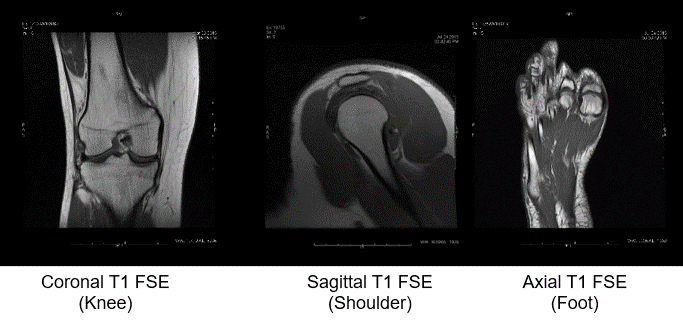

Now let’s look at some T1 weighted contrast. T1 contrast mostly shows anatomical size, shape, location. T1 (without the use of contrast agents) is usually used to display anatomy, not pathology.

Here we have a Coronal view of the knee, a sagittal view of the shoulder, and an axial view of the foot. All are Fast Spin Echo’s as we see the FSE indication. As you can also see, T1 weighted contrast has a very different appearance compared to T2 weighted contrast on an MRI image.